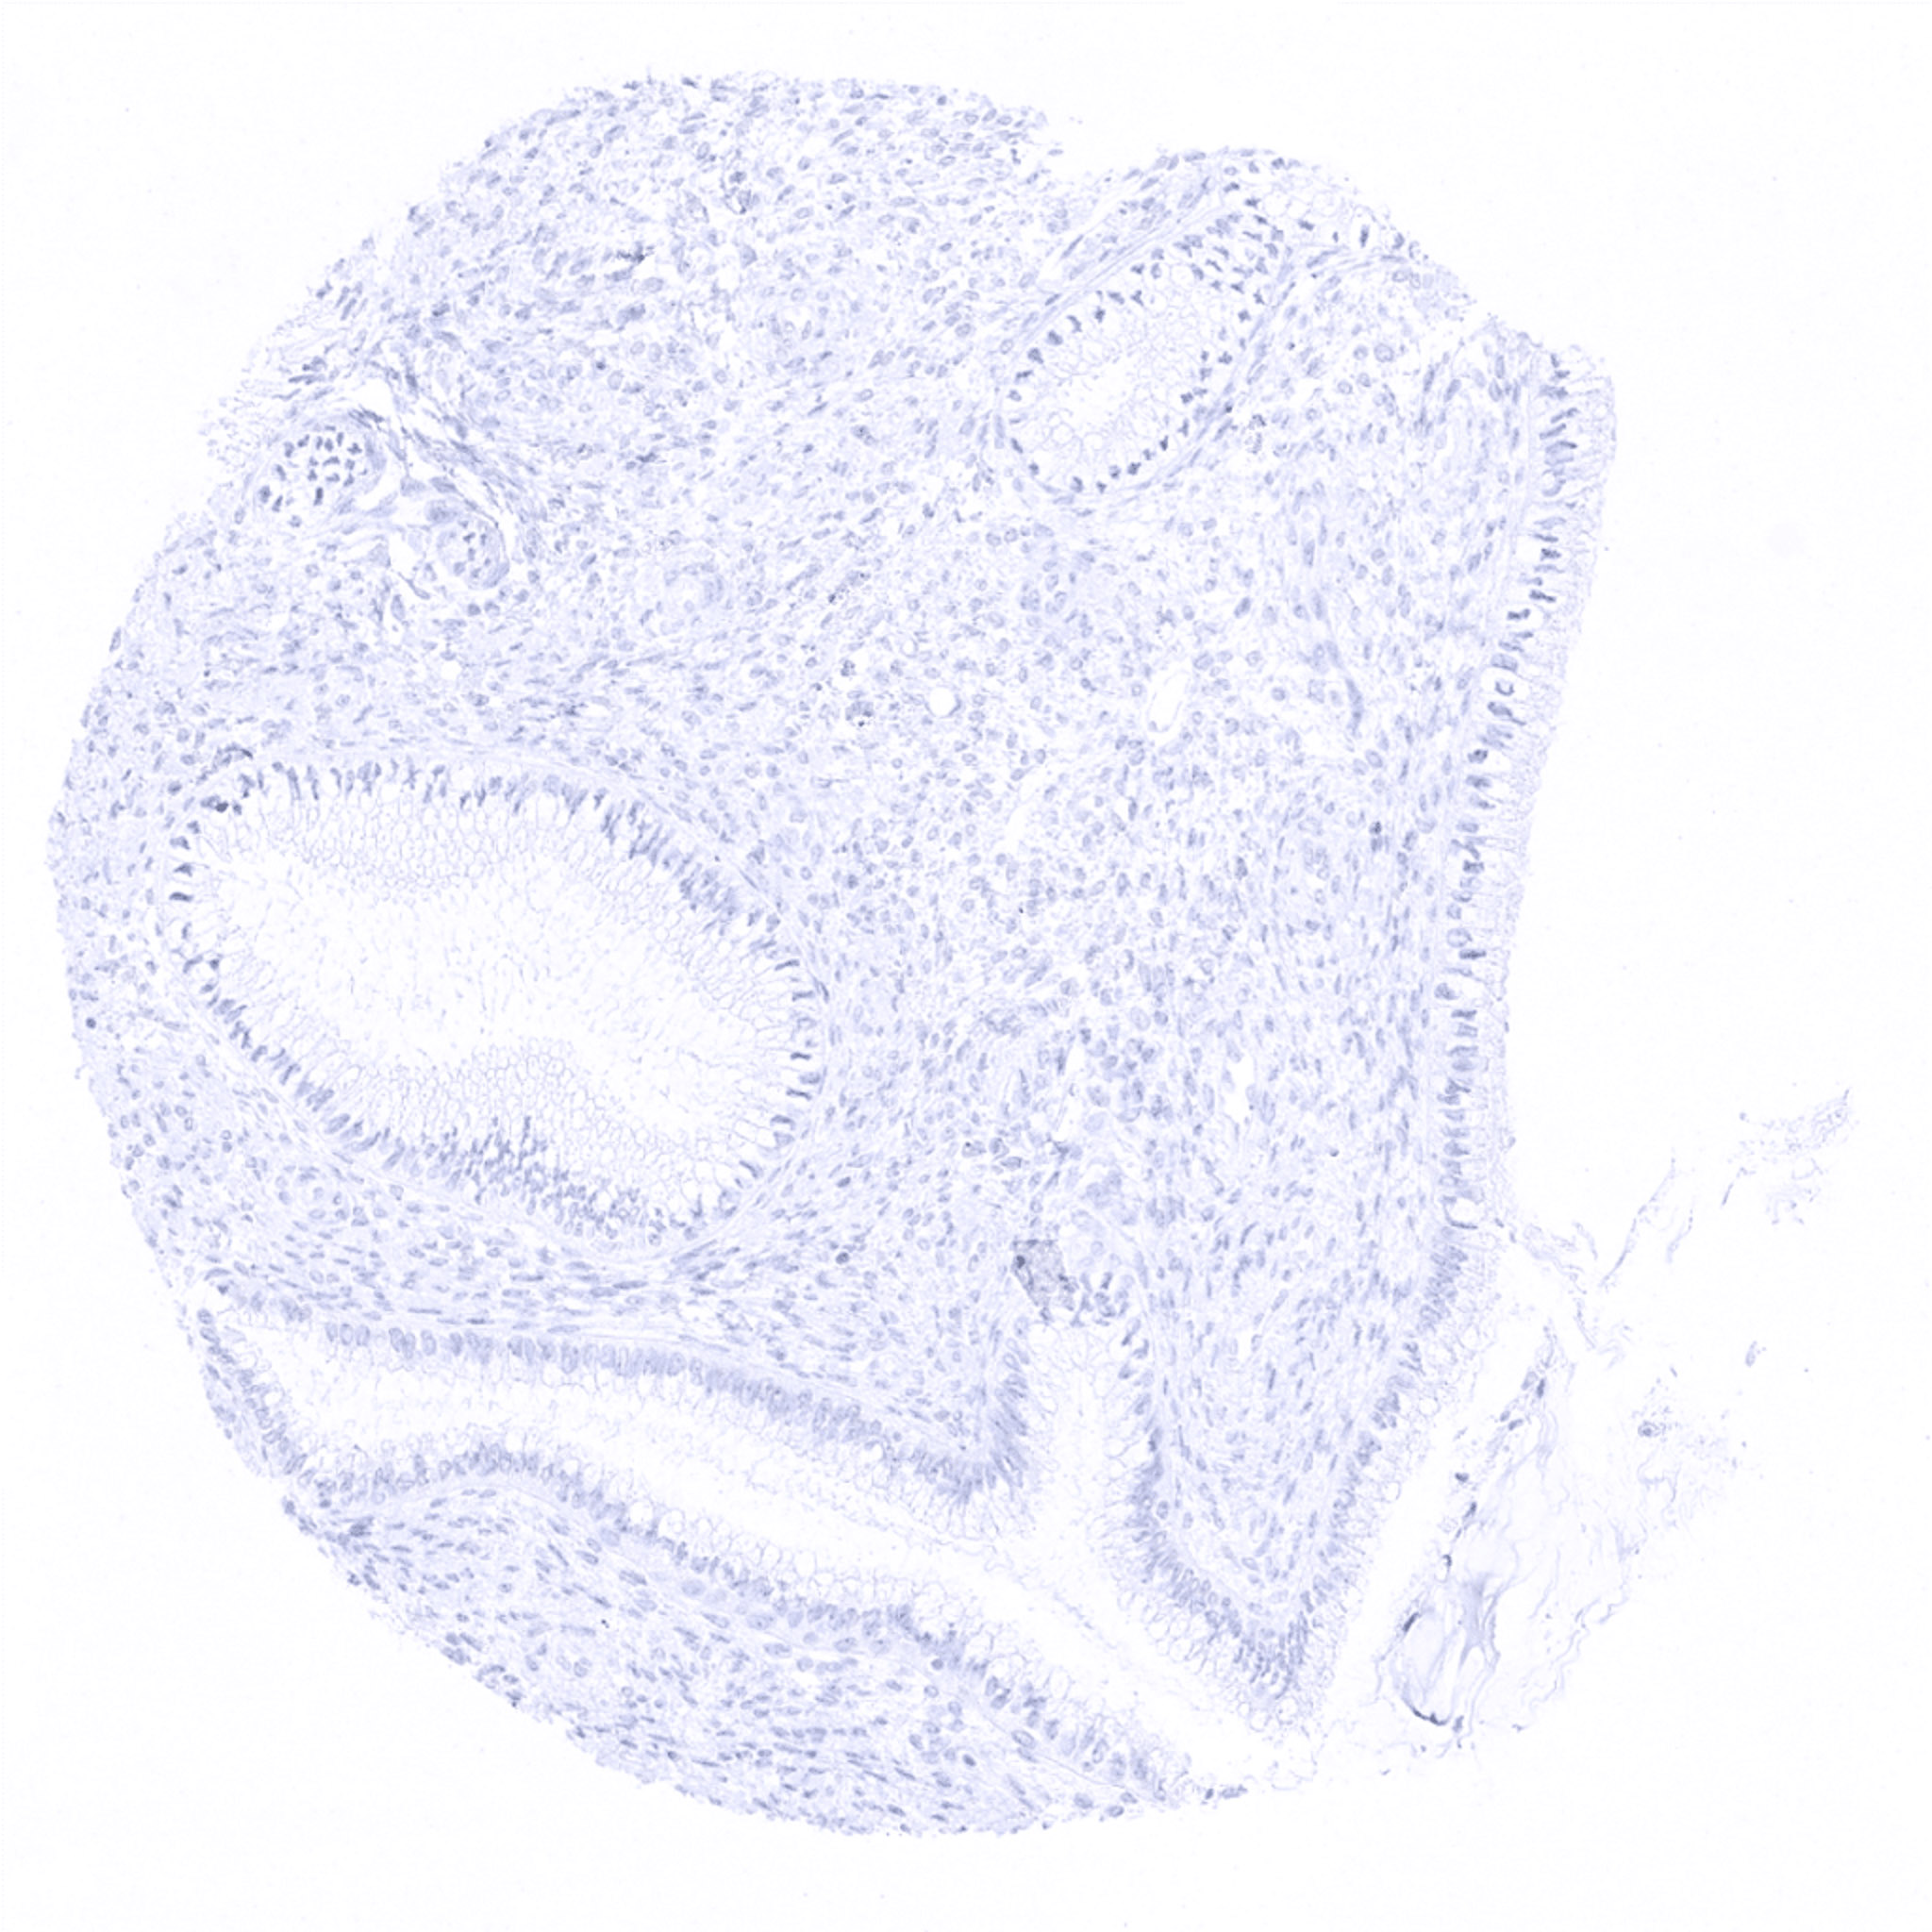

Ectocervix

Endocervix